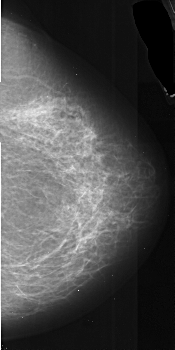

A_1036_1.RIGHT_MLO

RIGHT_MLO LINES 5491 PIXELS_PER_LINE 2881 BITS_PER_PIXEL 16 RESOLUTION 42 NON_OVERLAY